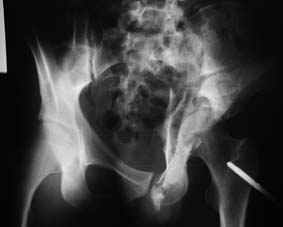

Все-таки надо бы начать не с КТ, а с обзорного снимка таза и косых проекций впадины.

Это обзорные и косые снимки

С уважением,

Привет, Леонид. Оскольчатый высокий двухколонный перелом в такие сроки трогать не надо, т.к. это про такие переломы сказано: "кто с ножом на Ж. пойдет тот в ней и останется...".